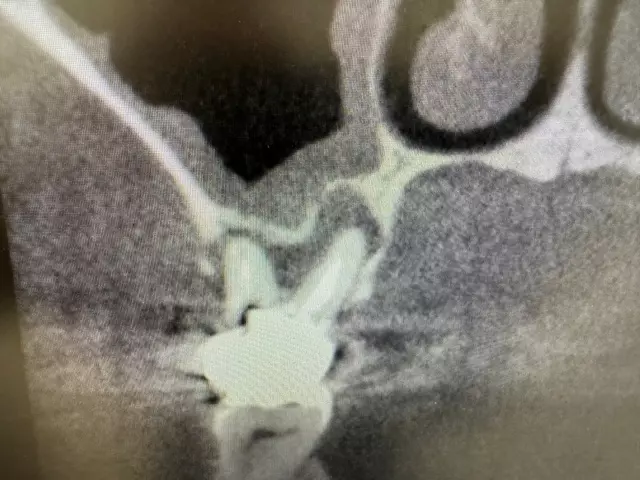

| 主訴 | 左下7番部 インプラント埋入 |

| 治療内容 | 左下7番部 インプラント埋入。 抜歯即時埋入。 抜歯後抜歯窩掻把。その後ワイドインプラント埋入。 |

時間は抜歯込みで20分程度でした。